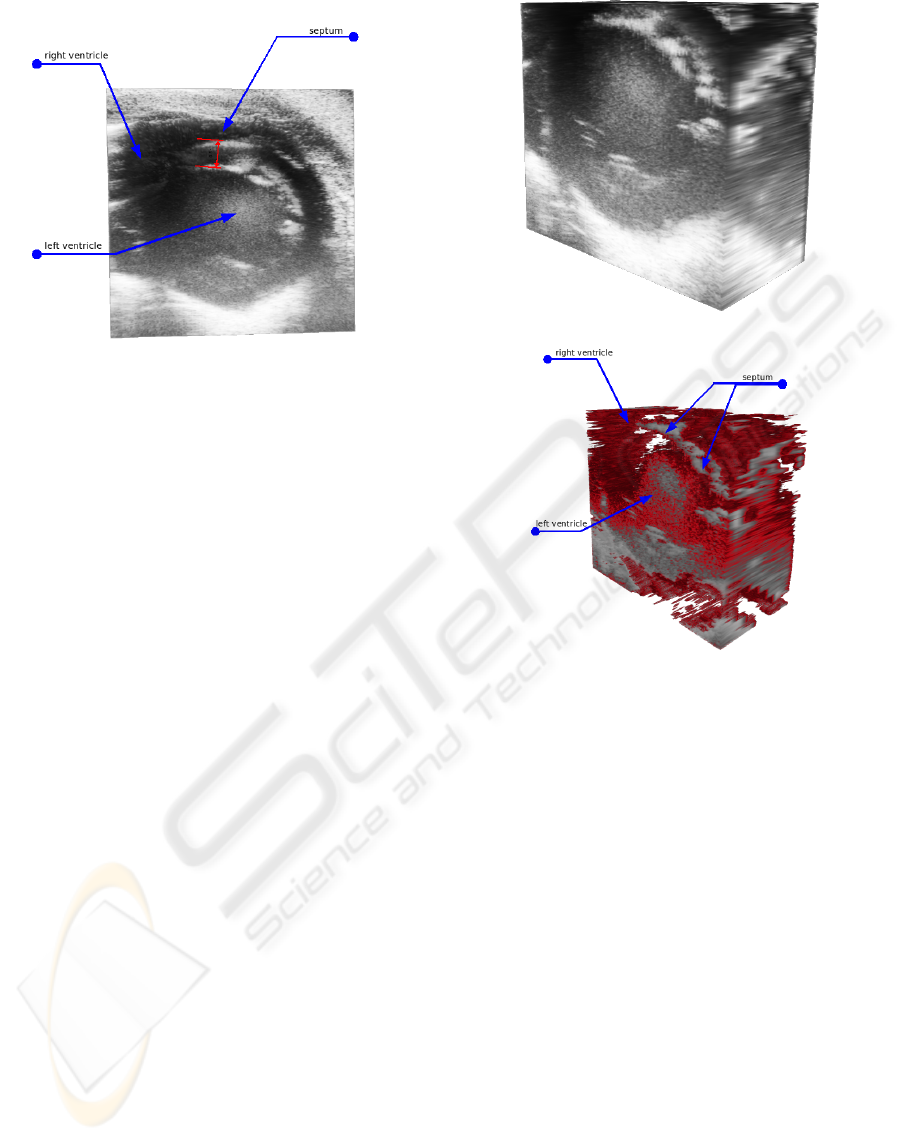

In our system setup we use a VisualSonics Vevo 770

small-animal US scanner for scanning mice in vivo. It

provides most common US scan modes, and supports

ECG-gated acquisition of 2D slices. It allows multi-

We use a special scanning mode which is a pro-

prietary variant of an ECG-gated scanning procedure.

The so-called EKV (ECG-based Kilohertz Visualiza-

tion) mode is a scanning technique, during which

multiple B-Mode images from consecutive heart peri-

ods are acquired and interpolated into a single, com-

plete heart period of the animal (VisualSonics, 2005).

Thus a complete heart period is represented by a set of

frames for each lateral position. Therefore, in using

the EKV-Mode in this paper, the creation of precise

volume ”stills” of the scanned organ simplifies the

frame synchronization routine significantly. Thus, by

choosing the corresponding frames out of each syn-

chronized frame set recorded at each lateral position,

a volume data set can be created for each phase of the

heart cycle. Subsequently, the volume data sets re-

constructed in this manner comprise a whole dynamic

data set collection.